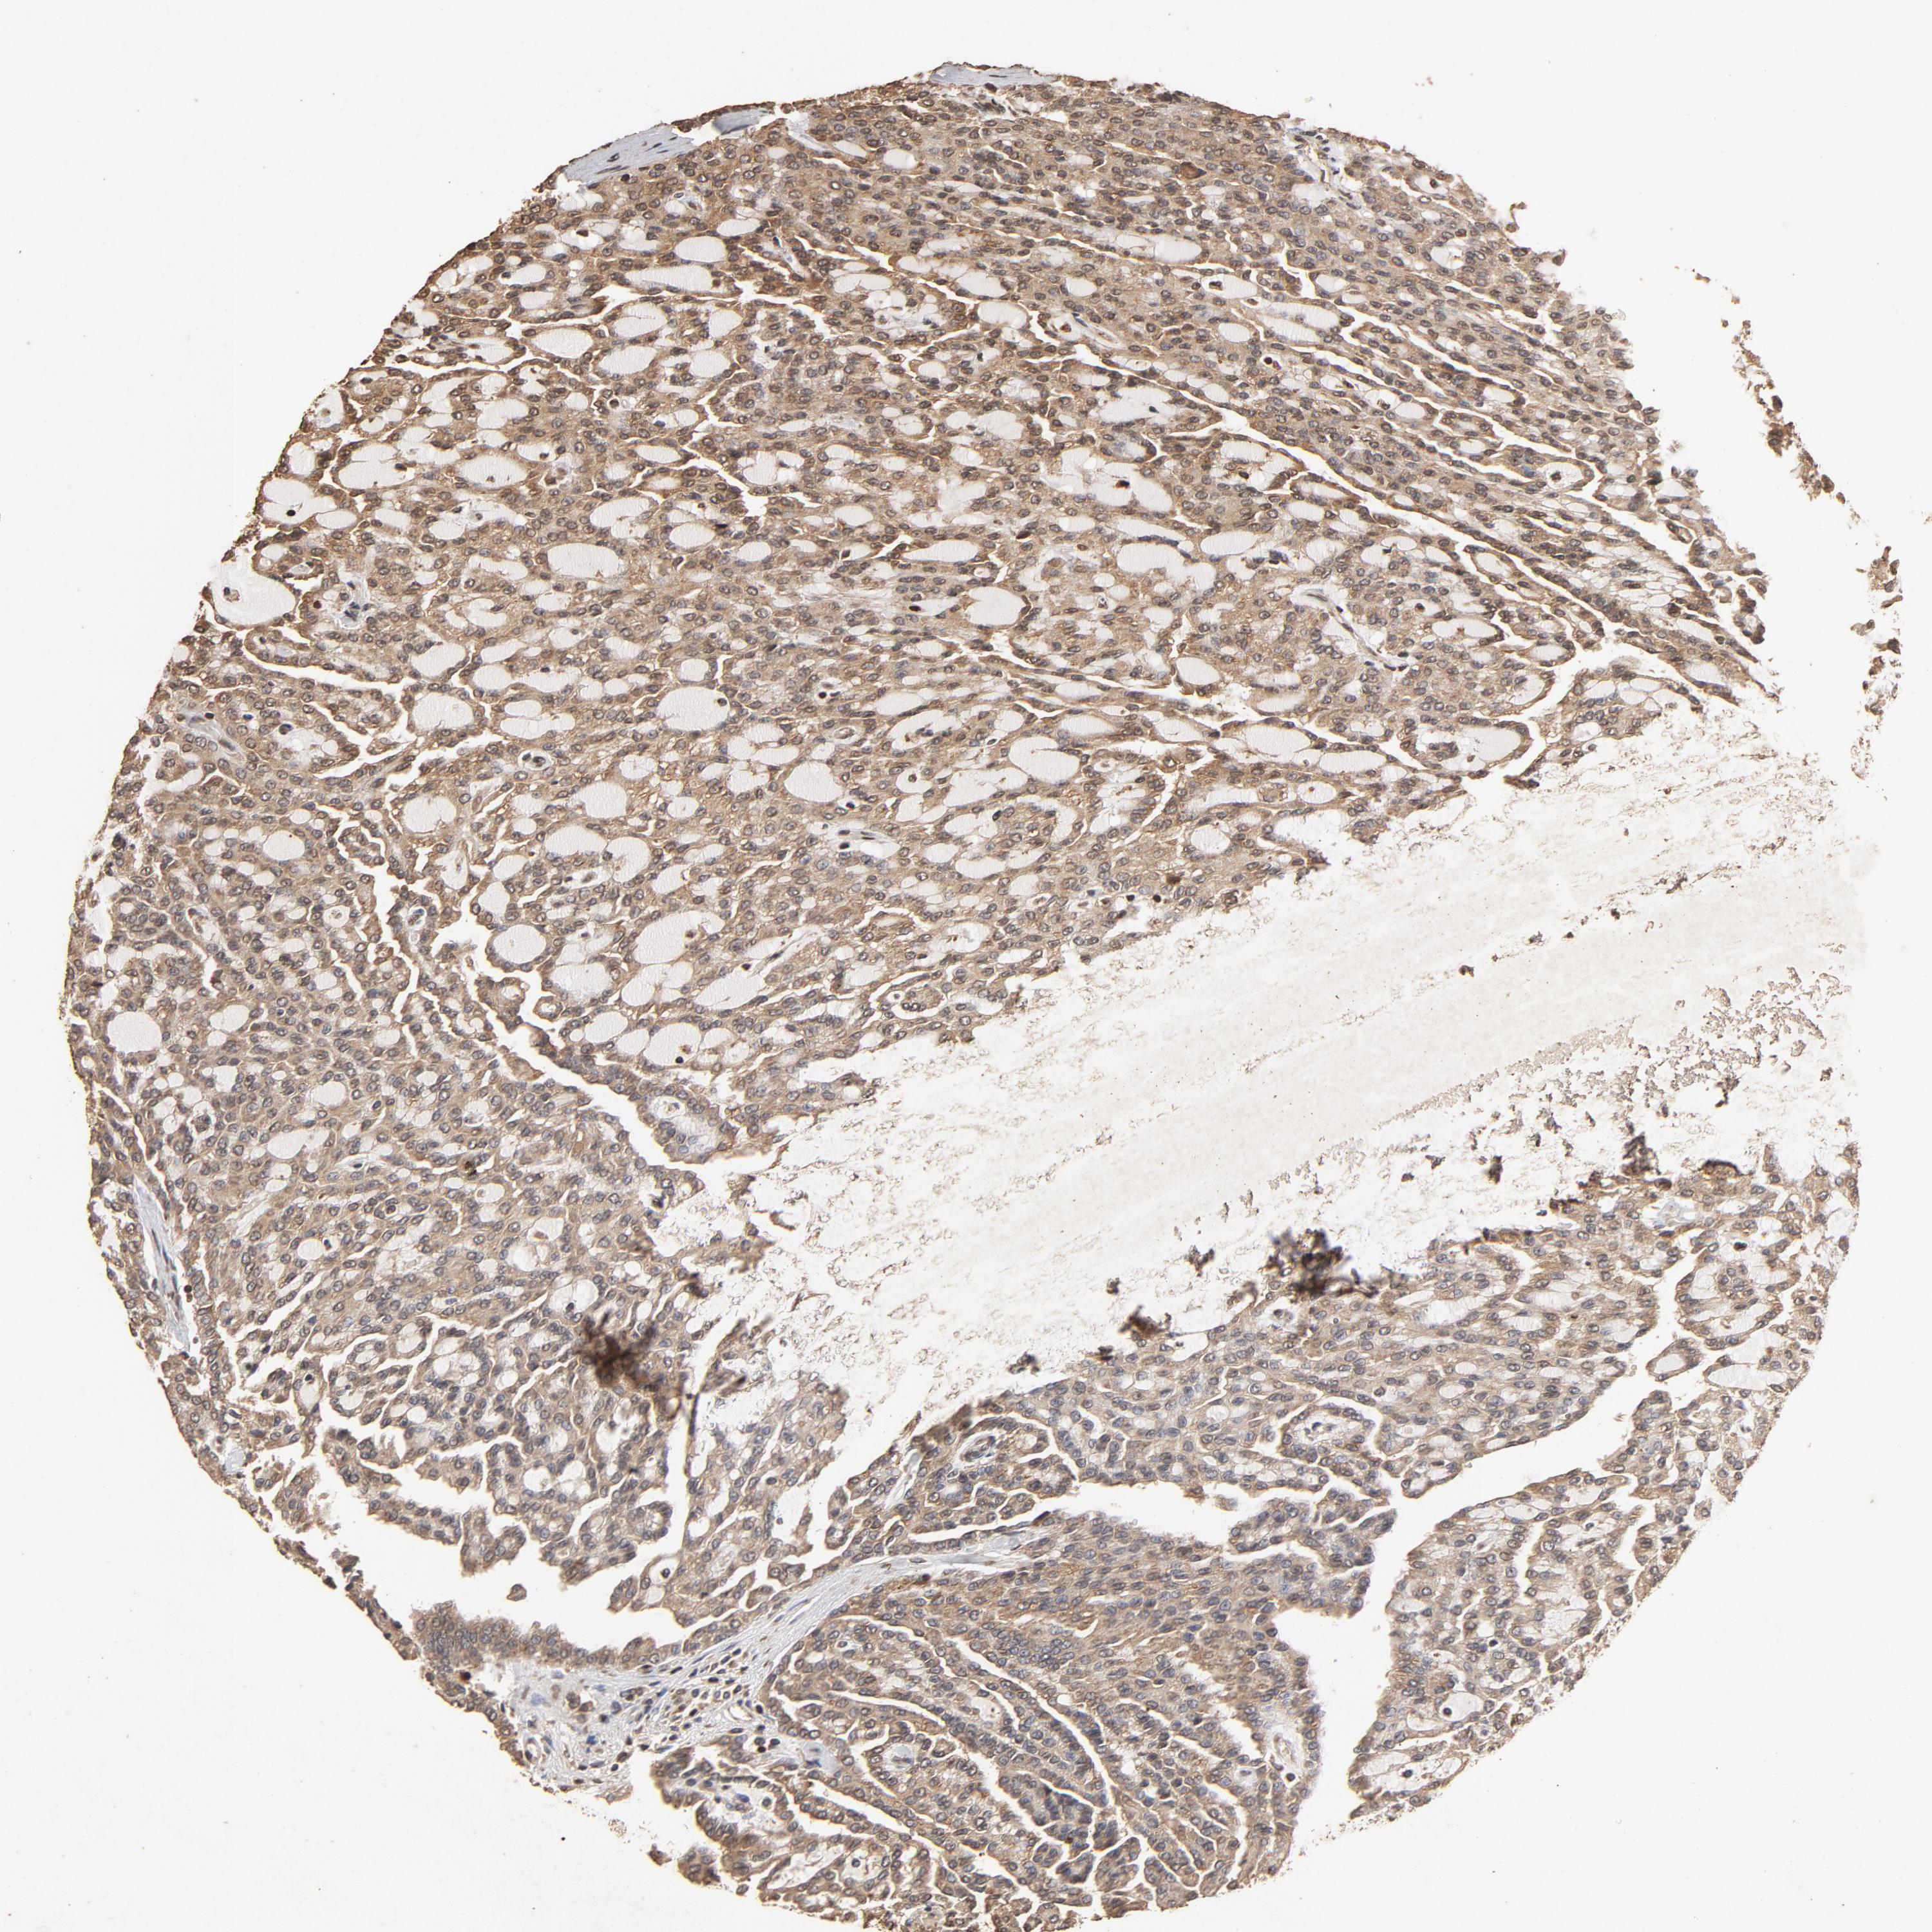

KIDNEY RENAL CLEAR CELL CARCINOMA (TCGA) - Interactive survival scatter ploti

The Survival Scatter plot shows the clinical status (i.e. dead or alive) for all individuals in the patient cohort, based on the same data that underlies the corresponding Kaplan-Meier plots. Patients that are alive at last time for follow-up are shown in blue and patients who have died during the study are shown in red.

The x-axis shows the expression levels (FPKM) of the investigated gene in the tumor tissue at the time of diagnosis. The y-axis shows the follow-up time after diagnosis (years). Both axes are complimented with kernel density curves demonstrating the data density over the axes. The top density plot shows the expression levels (FPKM) distribution among dead (red) and alive patients (blue). The right density plot shows the data density of the survived years of dead patients with high and low expression levels respectively, stratified using the cutoff indicated by the vertical dashed line through the Survival Scatter plot. This cutoff is automatically defined based on the FPKM cutoff that minimizes the p-score. The cutoff can be changed by dragging the vertical line or by entering a cutoff value in the square labeled "Current cut-off".

Under the Survival Scatter plot the p-score landscape (black curve; left axis) is shown together with dead median separation (red curve; right axis). Dead median separation is the difference in median mRNA expression between patients who have died with high and low expression, respectively. It is calculated as follows: median FPKM expression of dead patients with high expression - median FPKM expression of dead patients with low expression. This is intended to aid the user in visually exploring custom cutoffs and the associated p-scores and dead median separation.

Individual patient data is displayed and can be filtered by clicking on one or more of the category buttons on the top of the page. Categories describing expression level and patient information include: high, low, alive, dead, female, male and tumor stages. The scale of the x-axis can be toggled between linear and log-scale by clicking on the "x log" button. Mouse-over function shows TCGA ID, patient information and mRNA expression (FPKM) for each patient.

& Survival analysisi

Kaplan-Meier plots summarize results from analysis of correlation between mRNA expression level and patient survival. Patients were divided based on level of expression into one of the two groups "low" (under cut off) or "high" (over cut off). X-axis shows time for survival (years) and y-axis shows the probability of survival, where 1.0 corresponds to 100 percent.

CDC42 is potential prognostic, high expression is favorable in Kidney Renal Clear Cell Carcinoma (TCGA)

Best expression cut offi

Based on the FPKM value of each gene, patients were classified into two groups and association between prognosis (survival) and gene expression (FPKM) was examined. The best expression cut-off refers the FPKM value that yields maximal difference with regard to survival between the two groups at the lowest log-rank P-value. Best expression cut-off was selected based on survival analysis .

When clicking on this number, the vertical dashed line indicating cut-off, the interactive survival plot, and the Kaplan-Meier curve will be adjusted to show results based on the best expression cut-off.

: 155.68

TCGA RNA samplesi

RNA-seq data is reported as average FPKM (number Fragments Per Kilobase of exon per Million reads), generated by the The Cancer Genome Atlas (TCGA) .

Normal distribution across the dataset is visualized with box plots, shown as median and 25th and 75th percentiles. Points are displayed as outliers if they are above or below 1.5 times the interquartile range. FPKM values of the individual samples are presented next to the box plot.

Average pTPM 197.1

Number of samples 521